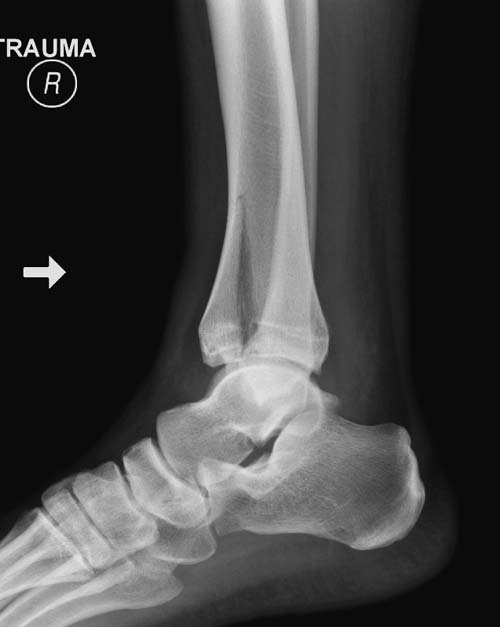

Первый случай, где перелом в результате падения с  небольшой высоты, где

мортиз рентген снимок показал отстутствие укорочения наружной

лодыжки и КТ срезы подсказали направления атаки. После такой фиксации

нет надобности в гипсовой повязке, брейс и через две недели движения в

суставе без нагрузки.